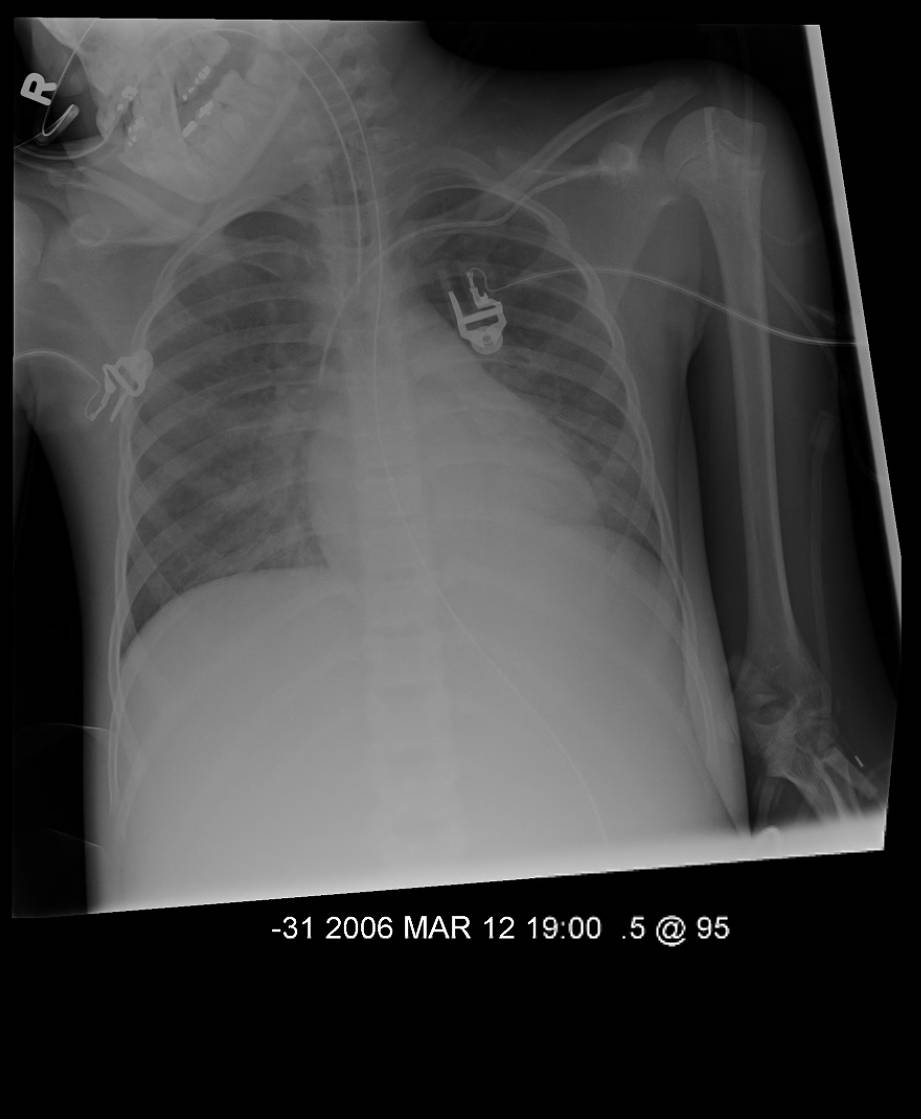

The respiratory status remained stable until Day 15 at which point she required increased ventilatory pressures (peak inspiratory pressure of 33 cm H20 and a PEEP of 12 cm H2O) and a FiO2 of 0.50. Her arterial blood gas was: pH 7.27; pAO2 73.5; pCO2 53.4; A-a gradient of 255.

A chest xray was obtained on Day 15

What is your interpretation?

figure 2